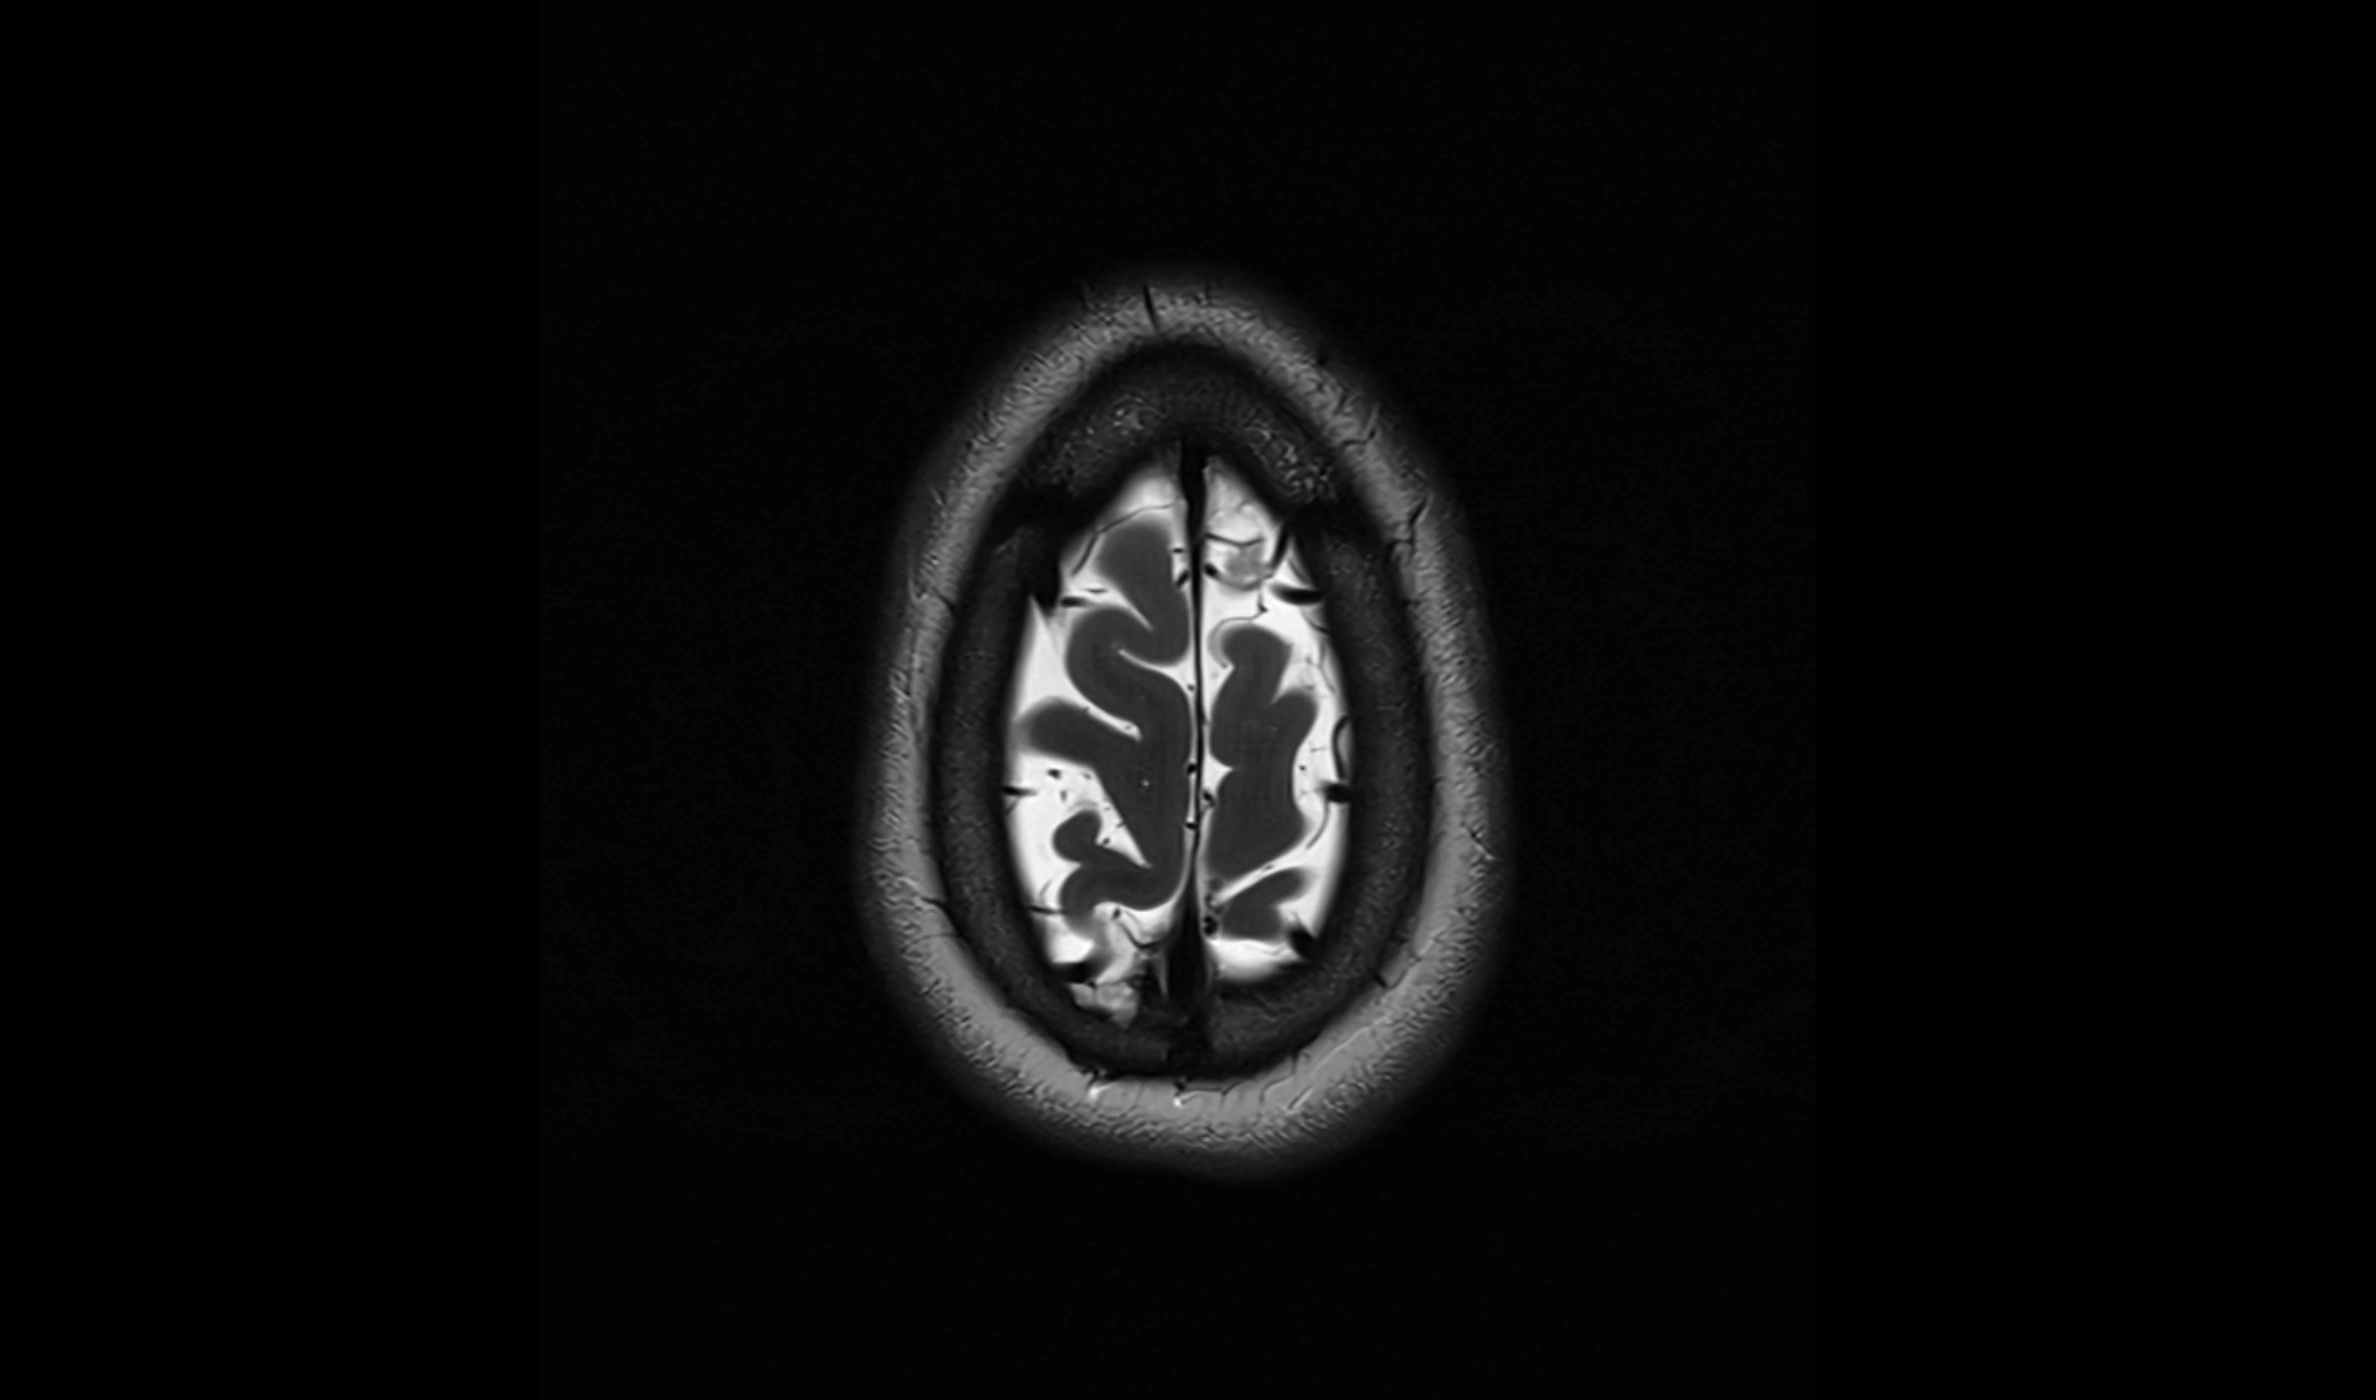

MRI images

image